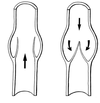

Fonction des valvules des MI

La fonction de ces valvules est de diriger le flux sanguin du réseau superficiel vers le réseau profond et du réseau profond vers le cœur.

- La thrombose veineuse, aussi appelée thrombophlébite, est un thrombus formé à l’intérieur d’une veine profonde ou superficielle, généralement au sein des sinus d’une valvule.

- La croissance du thrombus qui adhère à la paroi veineuse peut entraîner une occlusion complète de la lumière vasculaire et causer un syndrome obstructif responsable de phénomènes douloureux et d’œdème.

- La lyse du thrombus peut s’accompagner d’un remaniement des valvules et d’une insuffisance valvulaire à l’origine de la maladie post-phlébitique.